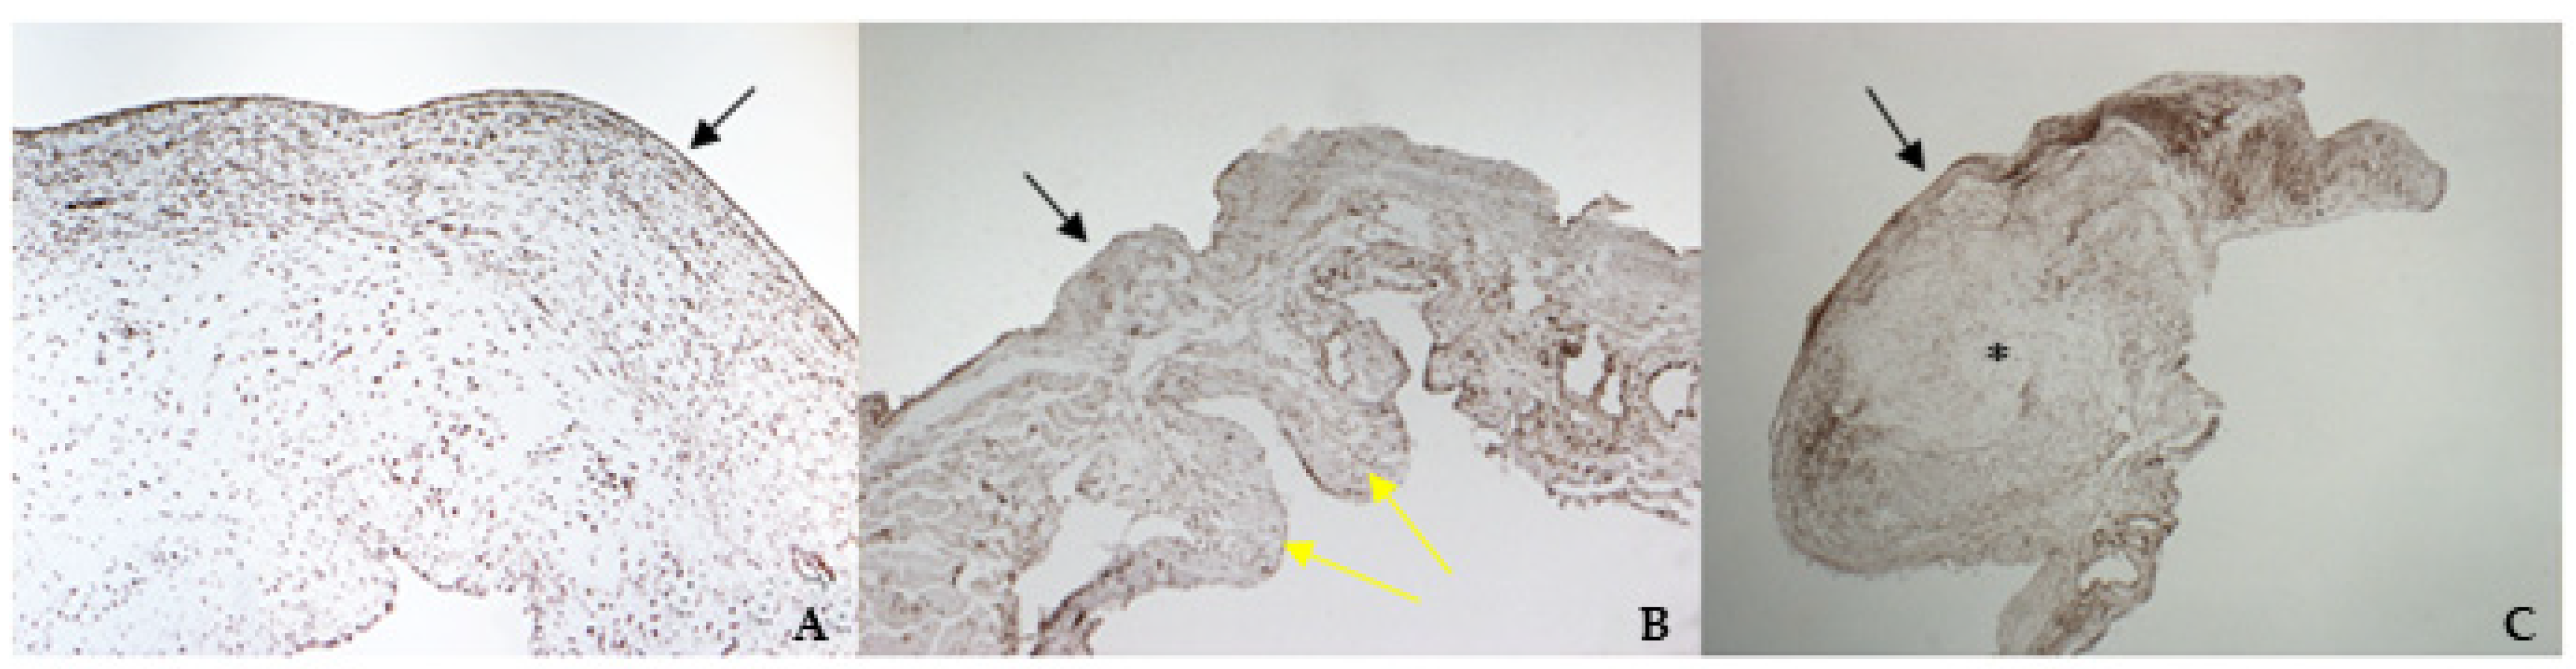

The histological examination of bovine and healthy canine mitral valves showed a normal stratified structure with a regular conformation of collagen (Figure 4A,B). Instead, the valve leaflets of the dog enrolled as pathological, presented severe myxomatous degeneration characterized by multifocal proliferation of spindle cells mixed to abundant eosinophilic intercellular matrix in the spongiosa and fibrosa layers, with collagen fragmentation. These cells demonstrated an heterogenous pattern, with central nuclei and scant homogeneous cytoplasm (Figure 4C and Figure 5C). IHC confirmed myxomatous degeneration in large areas of the leaflets, as shown by the double immunoreactivity to VIM and SMA of the spindle cells. The endocardial cells lining the valve leaflets in bovine and healthy canine mitral valves showed a diffuse immunoreactivity for vW factor corresponding to the endocardial layer, and occasional cells in the spongiosa layer were positive to SMA (Figure 6A,B). Differently, the endocardial cells layer of the pathological valve presented a widespread positivity to vW factor (Figure 6C).

Figure 4. The picture shows positivity to vimentin (VIM) in bovine (A) (magnification: 5×) and healthy (B) (magnification: 5×) and pathological (C) (magnification: 5×) canine mitral valves. Black arrows indicate the atrial aspect, while yellow arrows indicate the origin of the cordae tendinae (ventricular aspect). *: area of myxomatous degeneration.